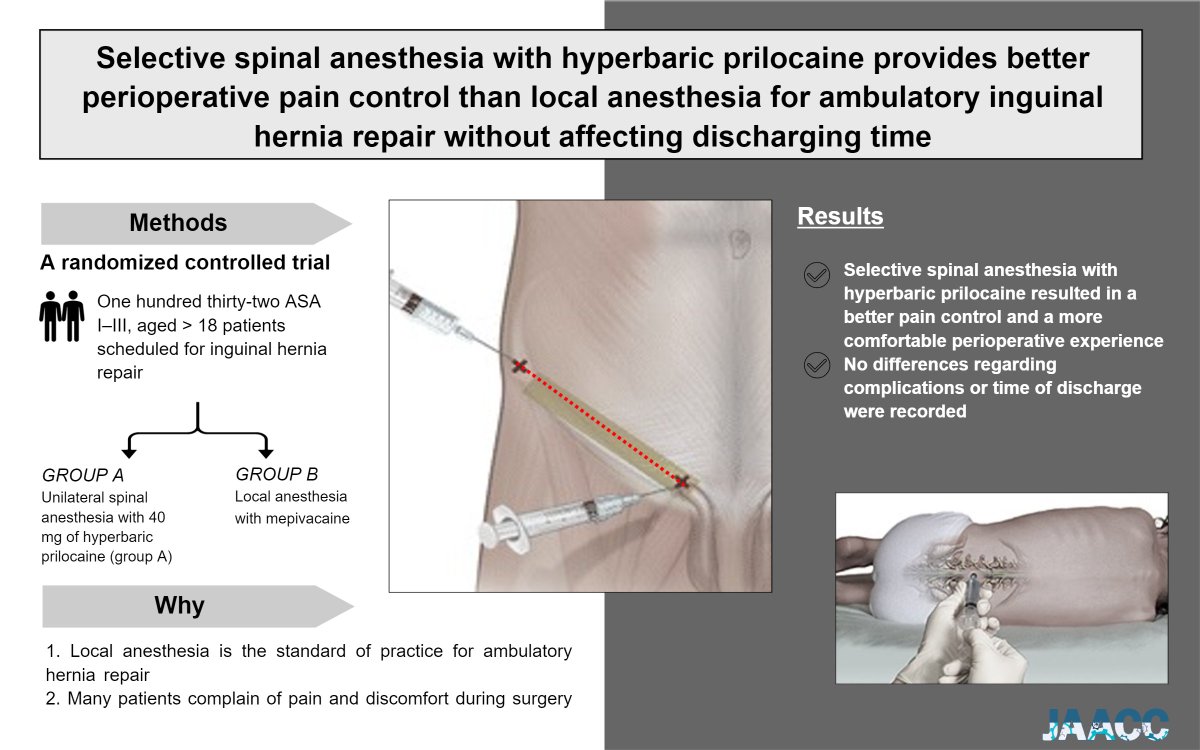

❓#Local or #neuraxial #anesthesia for #ambulatory #surgery❓ 💉Unilateral #spinal with hyperbaric #prilocaine may be the answer. ➡️Less pain and no impact on operating room turnover. 🔎 A randomized controlled trial 👉janesthanalgcritcare.biomedcentral.com/articles/10.11… #hernia Journal of Anesthesia, Analgesia and Critical Care